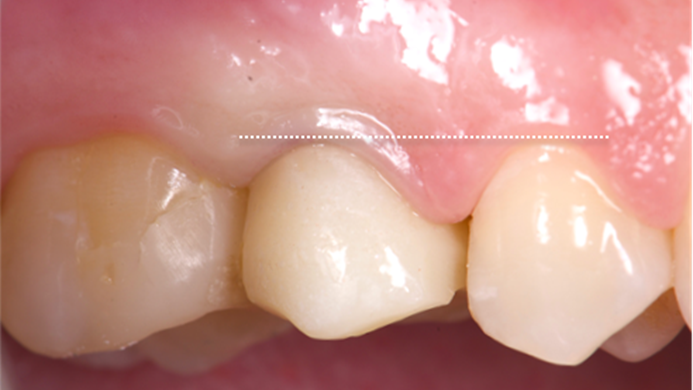

Clinical case: Extraction, immediate implant placement, & provisionalization

- Courtesy of Dr. Iulian Filipov, Romania -

AnyRidge, R2GATE, guided surgery, immediate placement, immediate provisionalization, initial stability, Dr. Iulian Filipov, #25, maxillary posterior, immediate loading, Mega ISQ

AnyRidge implant system, R2GATE, MEGA ISQ, Digital prosthesis